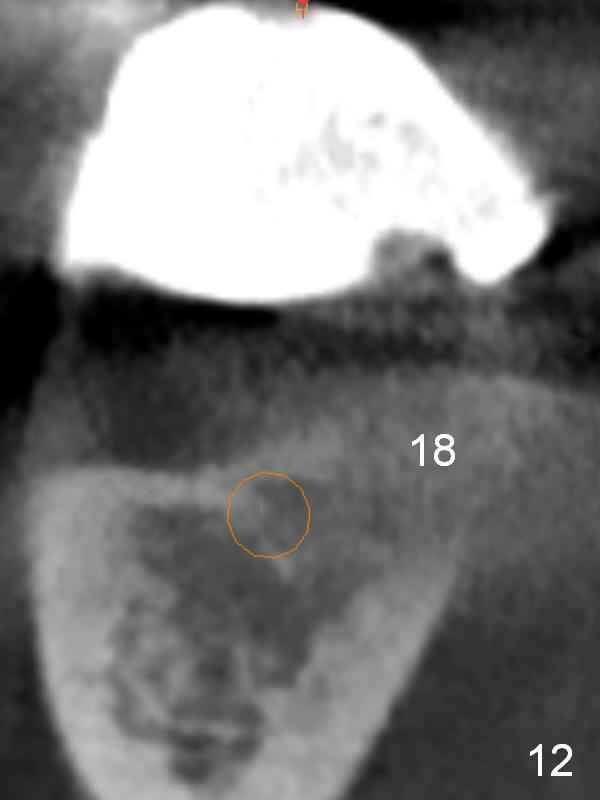

The patient wants to change unstable complete dentures to fixed ones. Because the problem of pain is associated with the lower left (Fig.1 the left Inferior Alveolar Nerve is more superficial), the lower arch will be reconstructed first. Totally 6 implants will be placed for bridges/crowns. Due to time constraint, four implants are placed at the 1st stage (#21, 22, 27 and 28 (Fig.4,5,8,9)); the lower denture will be retained immediately by ball abutments and soft relined. Two to three months later, two more implants will be placed (at #31 and 20, Fig.2,10). Note severe atrophy of the crest at #18 and 19 (Fig.11 and 12). If primary stability is achieved, a fixed immediate provisional will be fabricated.

In contrast to the upper arch, the bone density in the lower arch is high. The challenge is bone height. Short implants will be used (6 mm for #31 (Fig.2) and 8 mm for the majority of the others (at premolar and canine sites). If needed, extra implants will be placed at incisor sites (Fig.6,7 (implant can be longer)) and at #29 (Fig.3) . If a site is too small for a 3.8 mm 2-piece implant, a 1-piece one may be placed.